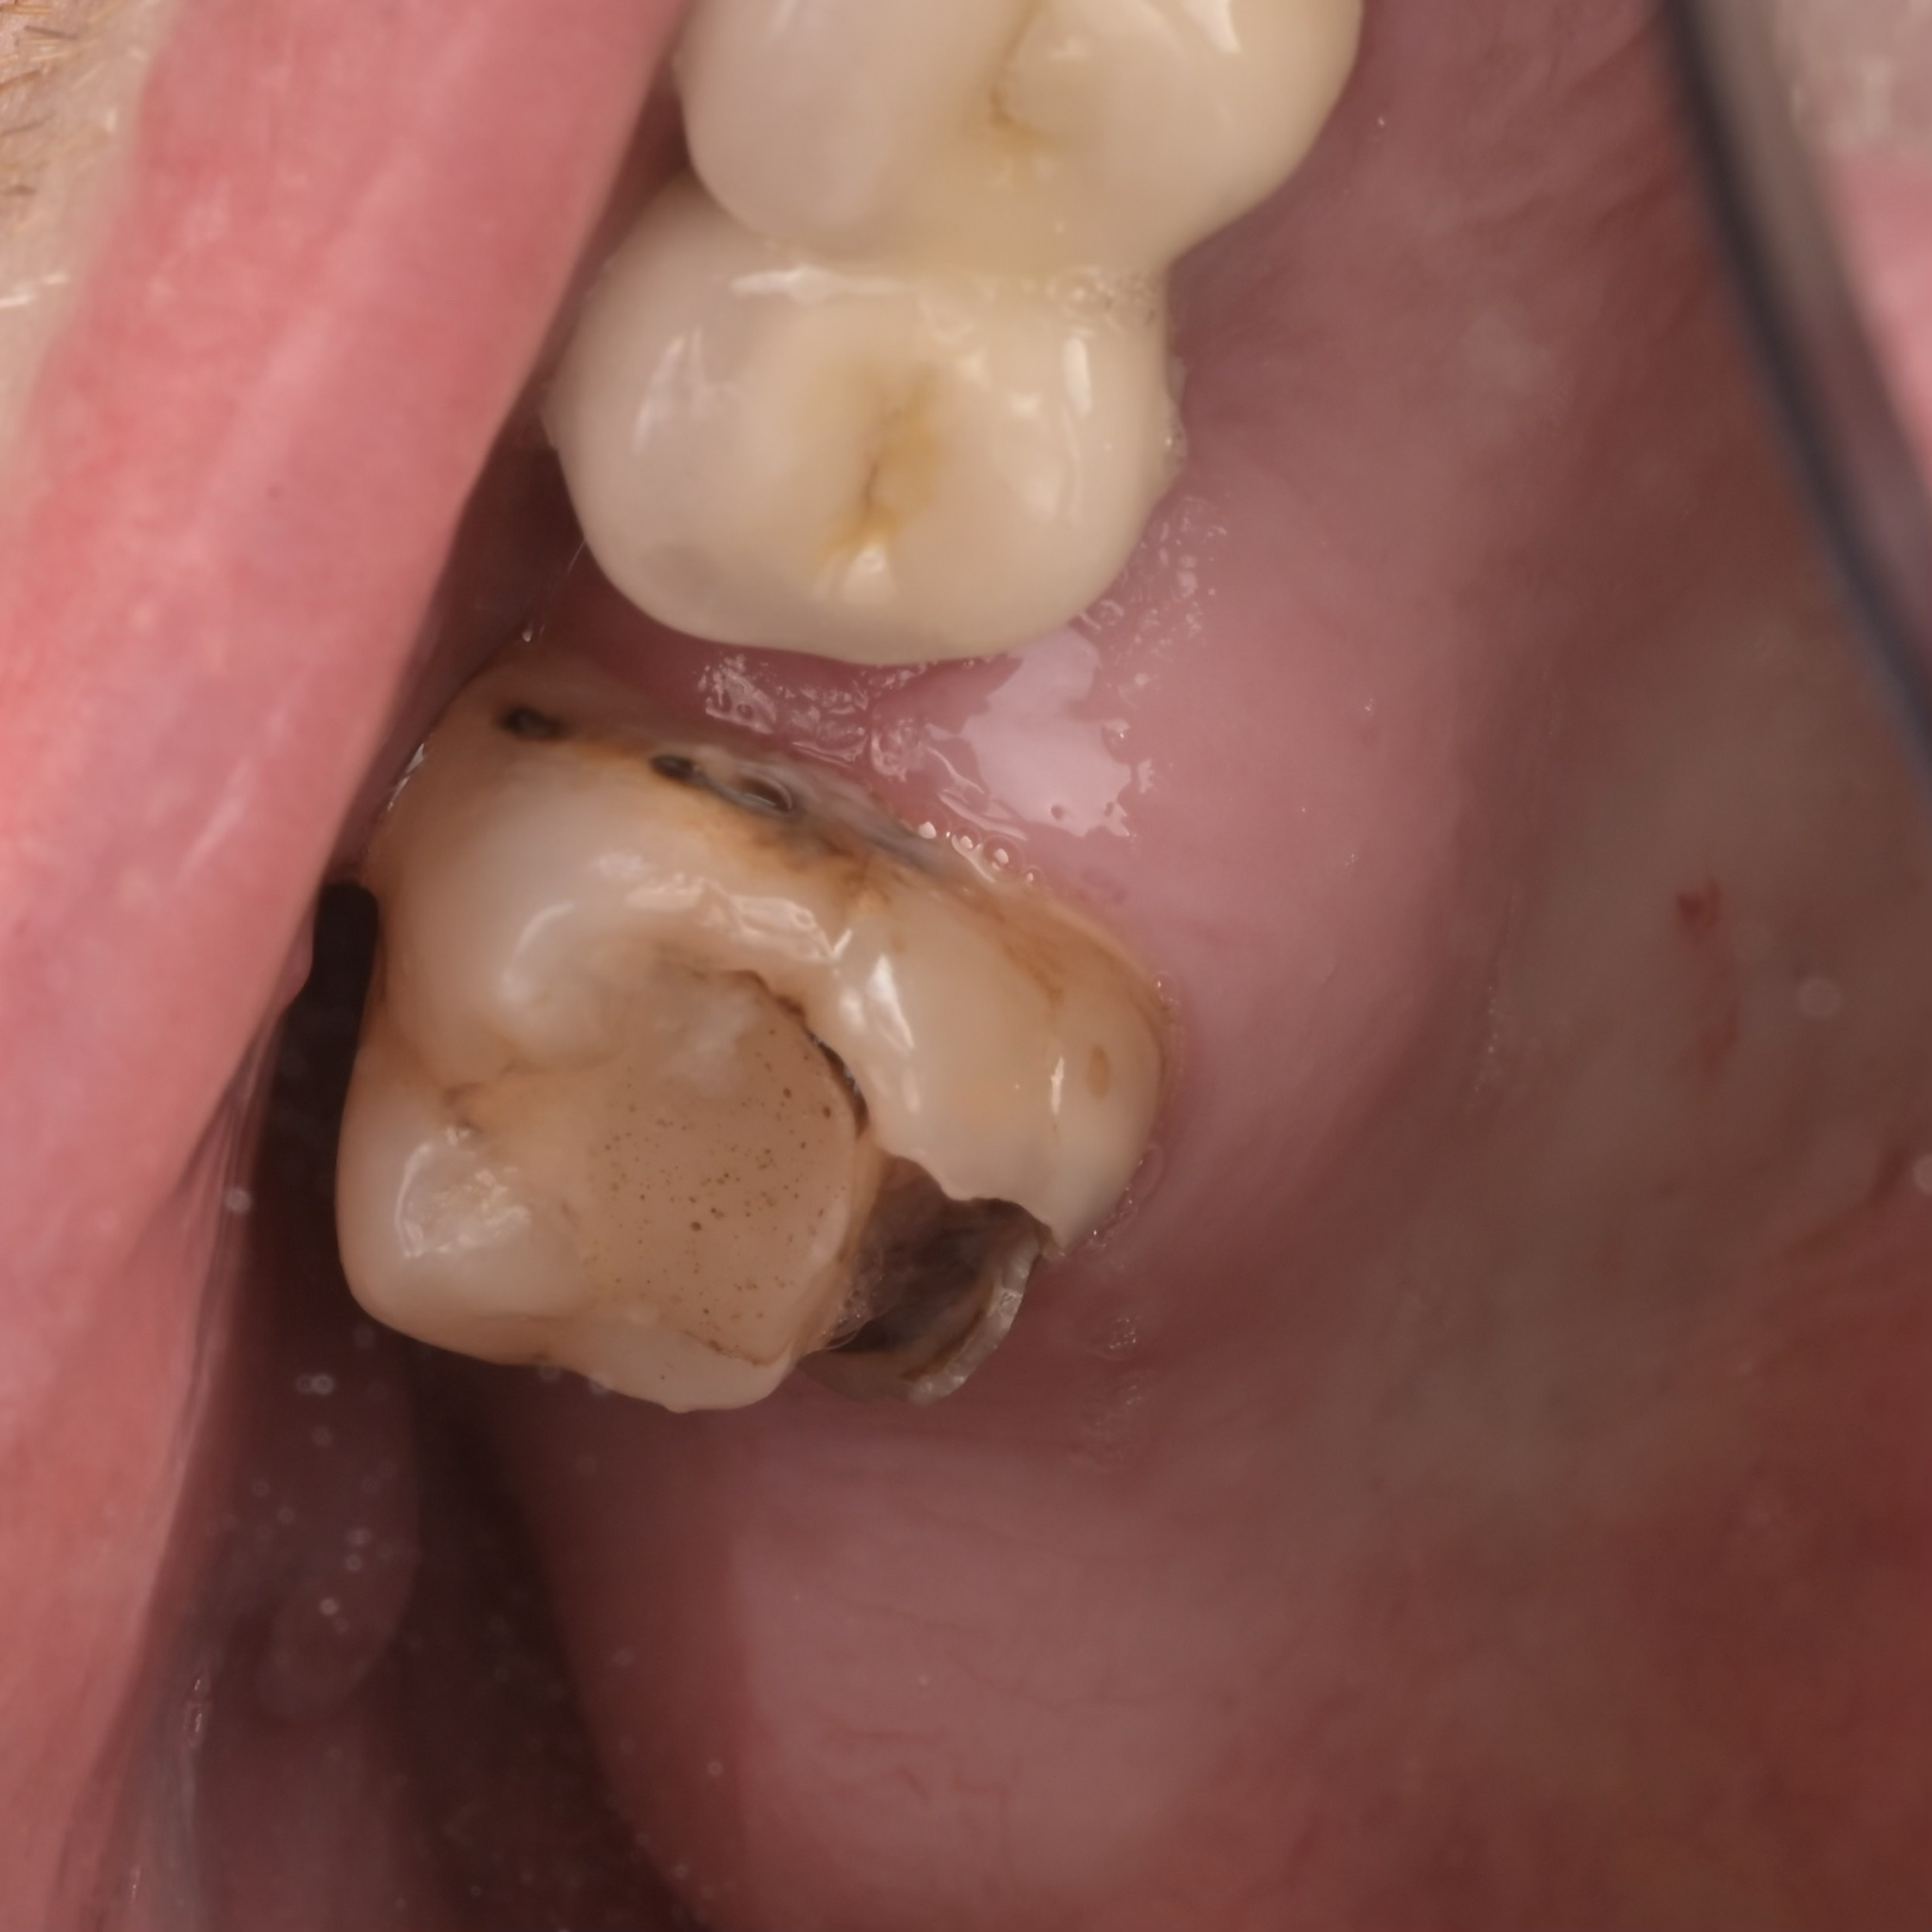

A biomimetikus fogászat egy modern megközelítés, melynek célja, hogy a fogak helyreállítását a fogorvos a természetes fog szerkezetét utánozva végezze el. A módszer kulcsa, hogy a fogat a lehető legkevésbé invazív módon kezelje, maximalizálva a megmaradt egészséges fogszövetet.

Célja, hogy az elkészült tömések és betétek (inlay, onlay) ugyanolyan erősek és rugalmasak legyenek, mint a természetes fog.

Ennek eléréséhez speciális ragasztási technikákat és bio-kompatibilis, üvegszál-erősítésű anyagokat használnak, melyek szorosan kötődnek a foghoz.

A hagyományos koronázással szemben, ahol sok ép foganyagot kell eltávolítani, a biomimetikus eljárásnál csak a sérült részeket távolítják el.

Ez segít megelőzni az úgynevezett „mély tömések” okozta gyökérkezelési szükségletet, mivel az ideg a fogban kevésbé sérül.

A megmaradó erős fogszövetnek köszönhetően a helyreállított fogak sokkal ellenállóbbak a repedésekkel és töréssel szemben.

A rágóerők egyenletesebben oszlanak el, így a fogat kevesebb stresszhatás éri rágás közben.

Ez a megközelítés hosszú távon stabilabb és tartósabb eredményt biztosít, csökkentve a jövőbeni fogászati beavatkozások szükségességét.

Összefoglalva: Az így elkészült tömések időtállóbbak, pontosabbak és jobban védik a megmaradt foganyagot, mint a hagyományos technikával elkészített tömések, a kutatások alapján, ez a jelenlegi ismereteink szerinti legmodernebb, evidence-based eljárás.